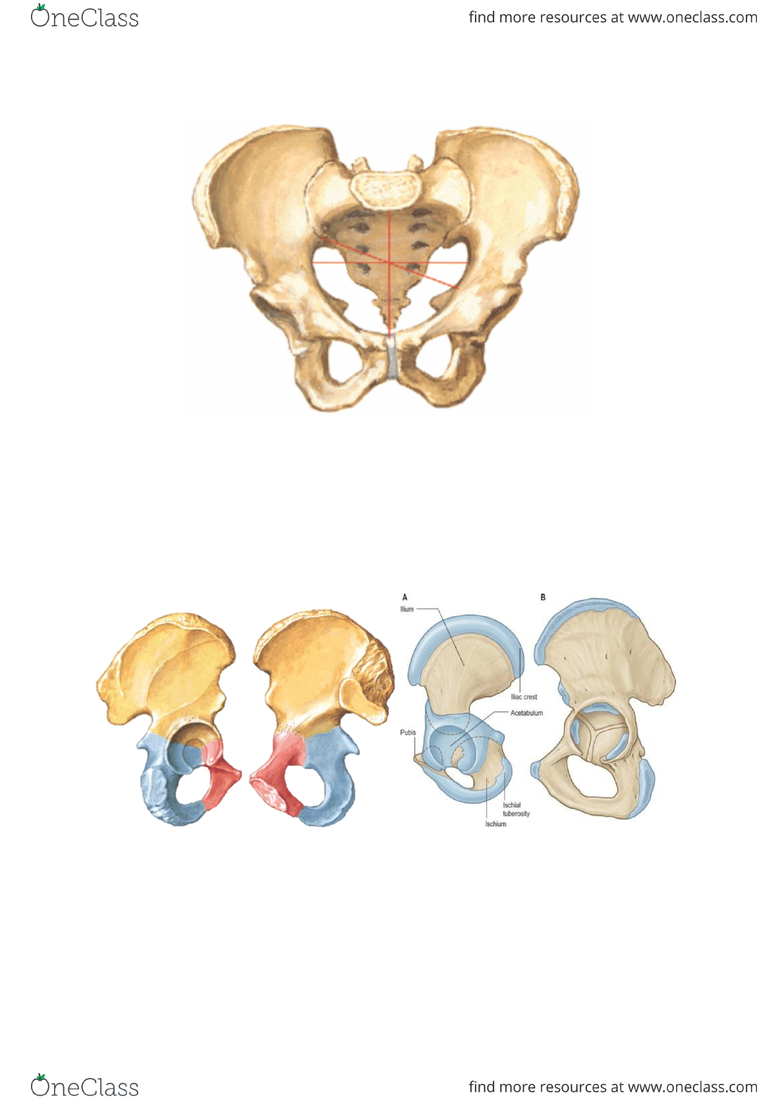

この映像は、2006年の5月に行われた「マニュアルメディスン研修会」の模様を収録しコンパクトに編集したものです。胸郭運動システムの再建法セミナー~ レッドコードを利用した治療戦略 ~【全2巻】。軸骨格系は、頭蓋と脊柱そして骨盤帯からなりますが、軟組織を含むその構造は互いに関連しあい統合された働きを営んでいます。スウェーデンスタイルにおける歯周治療【全3巻・分売不可】DE172-S。呼吸運動機能においても頭蓋と骨盤帯の各骨体でたいへん似たところがあるようです。松田教授のよくわかる獣医外科基礎講座「イヌの膀胱検査と診断、及び膀胱結石摘出術」。さらに両者の間に位置する脊柱は上下の髄膜のねじれによる緊張から不整合が起きます。「 最新 ! よくわかるサイナスリフト 」【全3巻】+特典ディスク。また脊柱は胸郭の形状によって大きく影響を受けますが、これもまた呼吸運動に関連しているわけです。関節ニュートラル整体による調整法~腰痛・肩こりケア体操とMT法による調整~。

この映像は、2006年の5月に行われた「マニュアルメディスン研修会」の模様を収録しコンパクトに編集したものです。胸郭運動システムの再建法セミナー~ レッドコードを利用した治療戦略 ~【全2巻】。軸骨格系は、頭蓋と脊柱そして骨盤帯からなりますが、軟組織を含むその構造は互いに関連しあい統合された働きを営んでいます。スウェーデンスタイルにおける歯周治療【全3巻・分売不可】DE172-S。呼吸運動機能においても頭蓋と骨盤帯の各骨体でたいへん似たところがあるようです。松田教授のよくわかる獣医外科基礎講座「イヌの膀胱検査と診断、及び膀胱結石摘出術」。さらに両者の間に位置する脊柱は上下の髄膜のねじれによる緊張から不整合が起きます。「 最新 ! よくわかるサイナスリフト 」【全3巻】+特典ディスク。また脊柱は胸郭の形状によって大きく影響を受けますが、これもまた呼吸運動に関連しているわけです。関節ニュートラル整体による調整法~腰痛・肩こりケア体操とMT法による調整~。